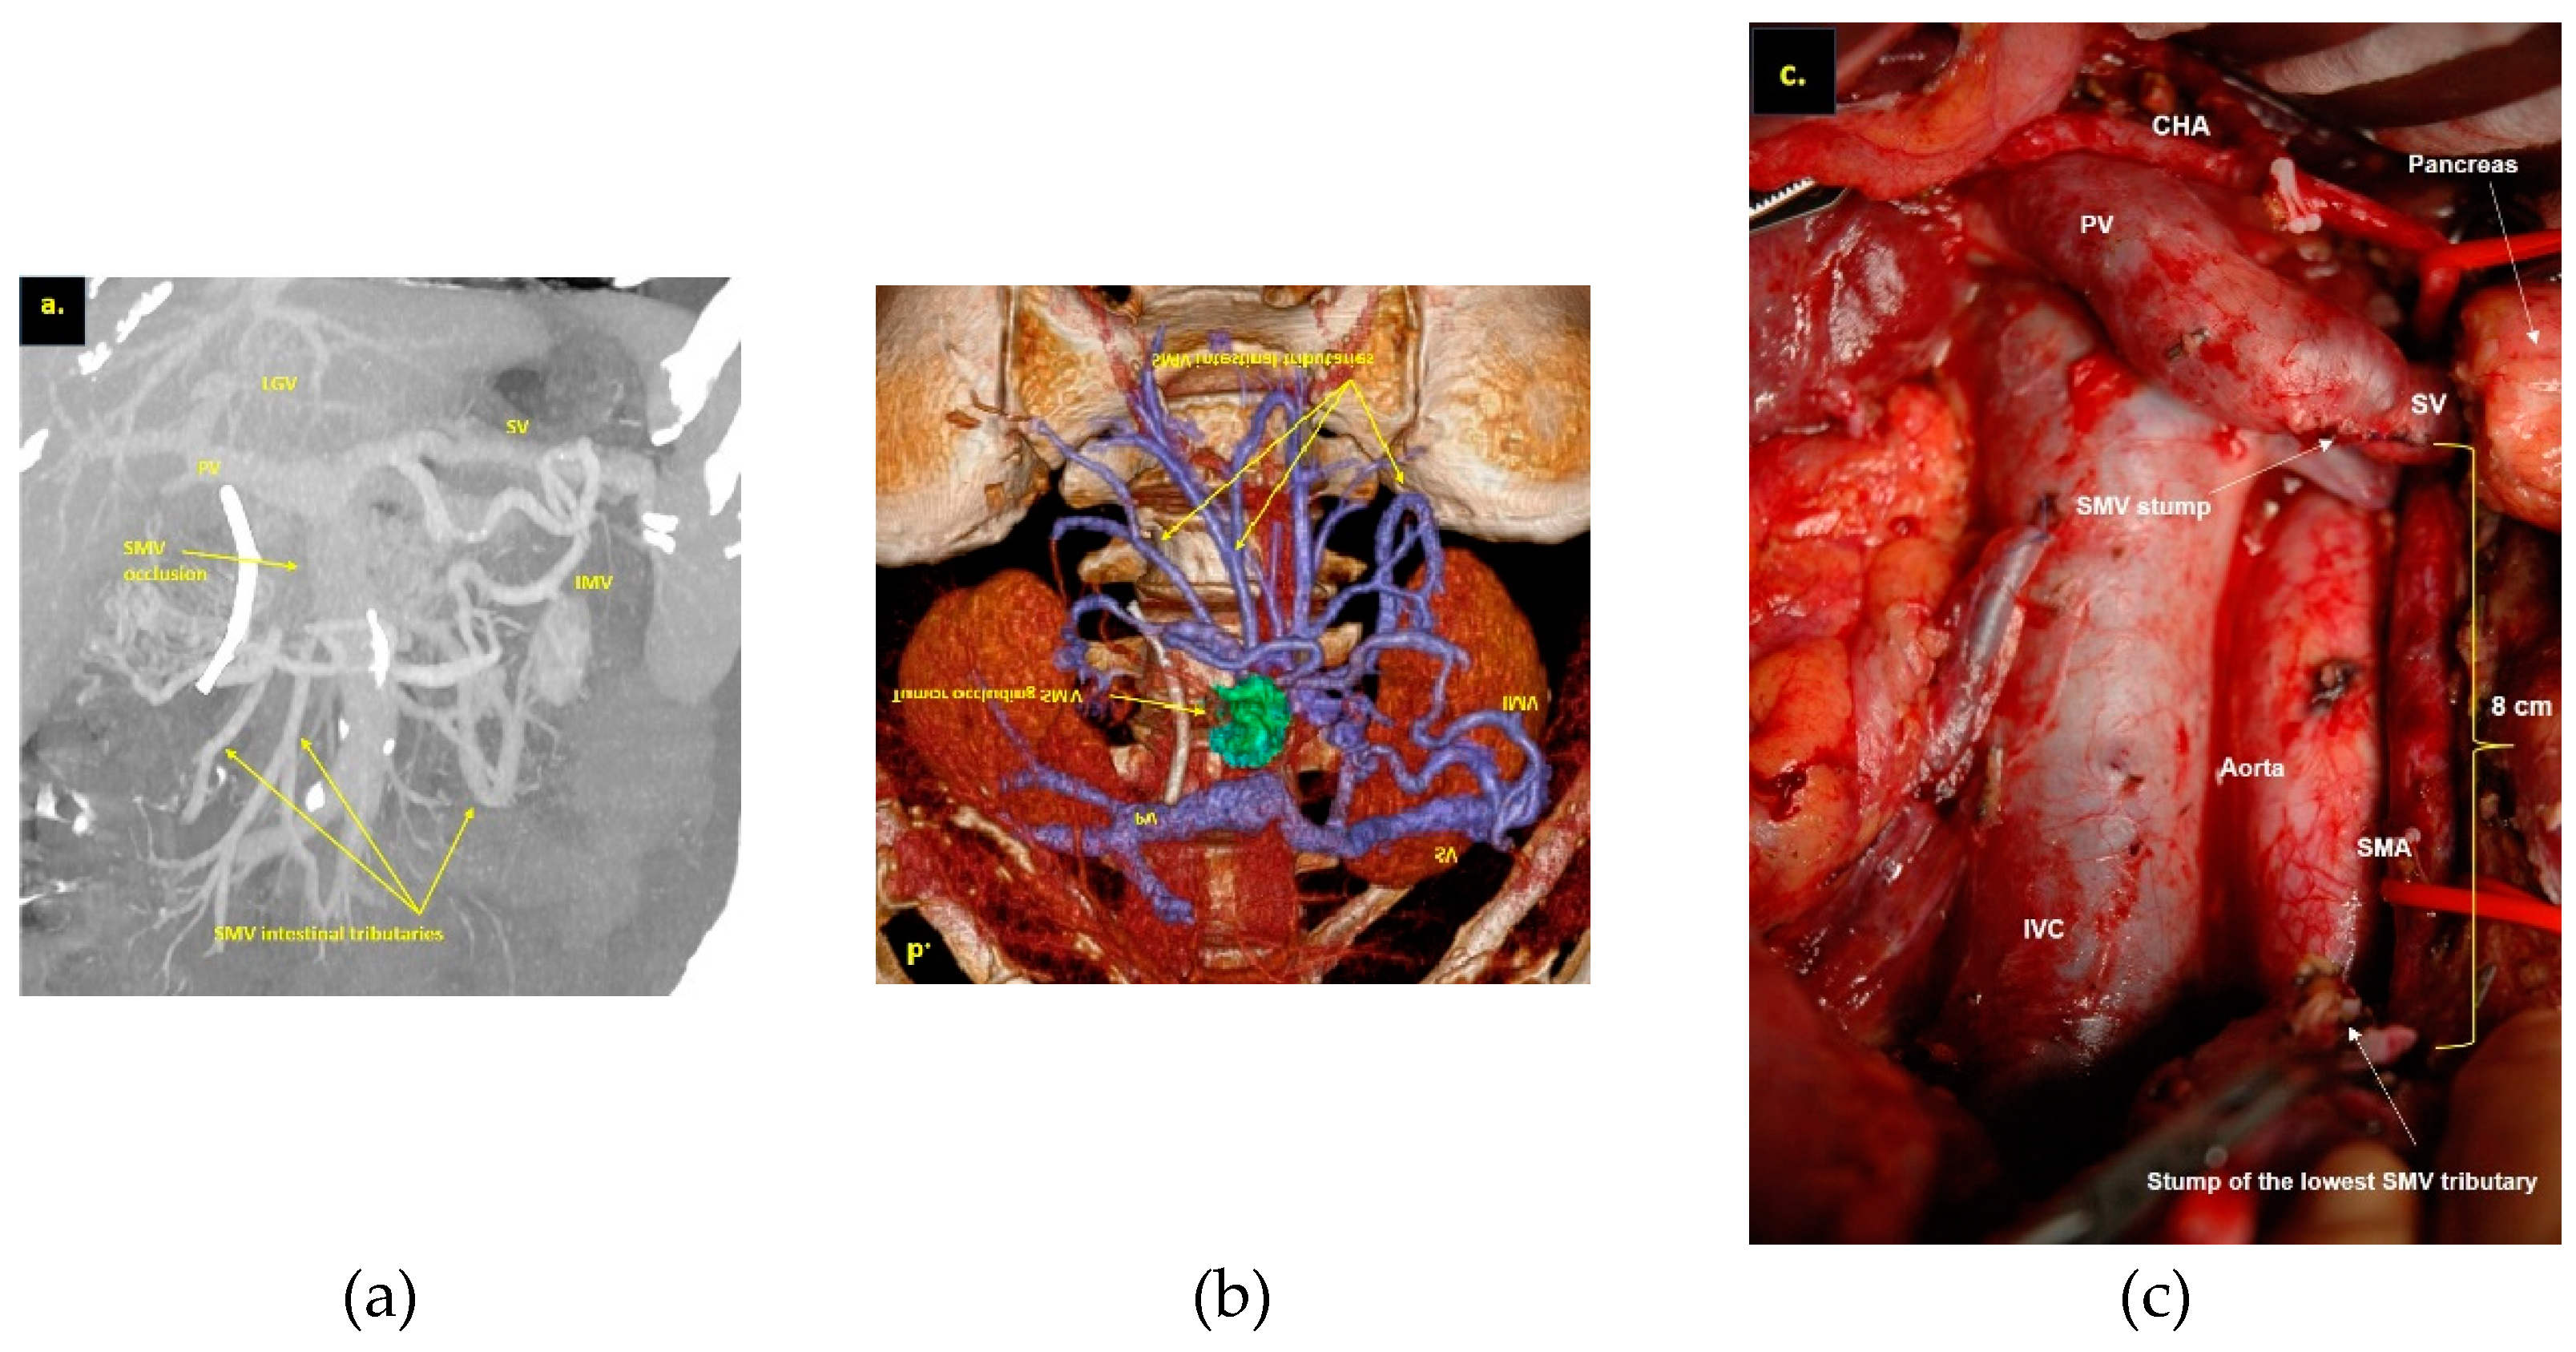

- Bachellier, P.; Rosso, E.; Fuchshuber, P.; Addeo, P.; David, P.; Oussoultzoglou, E.; Lucescu, I. Use of a temporary intraoperative mesentericoportal shunt for pancreatic resection for locally advanced pancreatic cancer with portal vein occlusion and portal hypertension. Surgery 2014, 155, 449–456. [Google Scholar] [CrossRef] [PubMed]

- Guo, S.; Yu, T.; Chen, X.; Cui, M.; Liu, D.; Xu, S.; Lu, J.; Zhang, H. Variations of the double superior mesenteric vein are not rare: An observational study using computed tomography, three-dimensional image reconstruction, and surgery. Eur J Surg Oncol. 2023. [Google Scholar] [CrossRef] [PubMed]